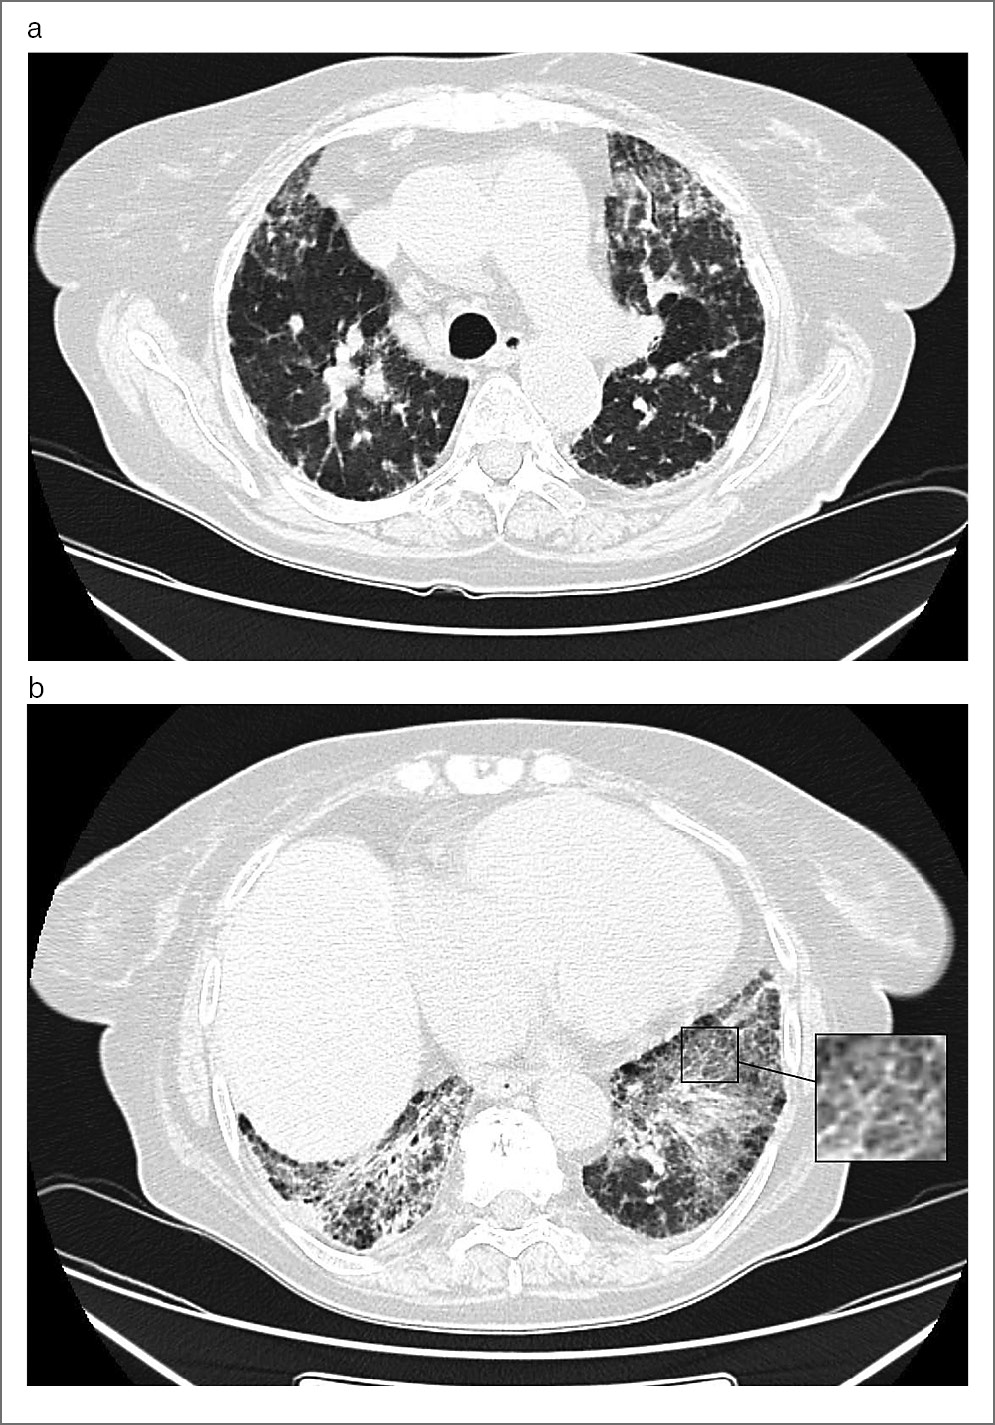

Анализ группы пациентов с фГП показал, что симптом «матового стекла» выявлен у 46 (88,5%) пациентов. Распределение этого признака в зависимости от степени выраженности показало, что обычно «матовое стекло» не являлось преобладающим симптомом и занимало относительно небольшой объем легочной паренхимы. Так, 1-я степень выявлена у 32 (61,5%) пациентов, 2-я степень – у 8 (15,4%) пациентов, 3-я степень – у 3 (5,8%) пациентов и 4-я степень – у 3 (5,8%) пациентов. Пример распределения симптома «матового стекла» продемонстрирован на рис. 1.

Рис. 1. Женщина, 64 года, фГП, ВРКТ: a – аксиальный срез. Распространенные участки уплотнения по типу «матового стекла» в верхних долях обоих легких, «мозаичная плотность» в виде трех плотностей; b – аксиальный срез. Распространенные участки «матового стекла», на фоне которых видны ретикулярные изменения (увеличенный фрагмент), формирующие симптом «хаотичного мощения», также определяется «мозаичная плотность» с картиной трех плотностей.